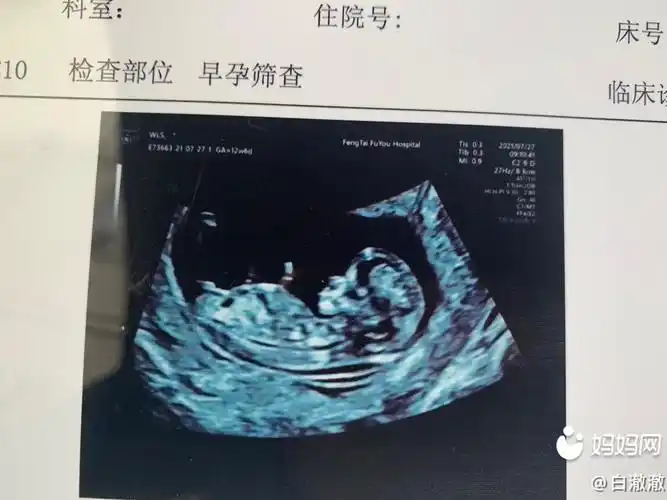

nt成功,看得出男宝女宝么?

12周nt都说我生女孩几率很大很期待